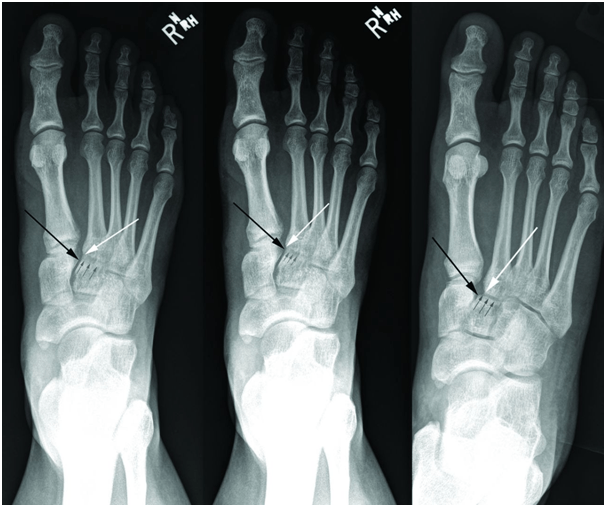

In weight bearing anteroposterior radiographs, the medial border of the second metatarsal base should be co-linear with the medial border of the intermediate cuneiform when the joint is uninjured (figure 2). In some cases, malalignment is obvious in the radiography (figure 3). Adequate anteroposterior radiographs must show a tangential view of the second tarsometatarsal joint (figure 1, right) since views oblique to the joint may miss subtle displacements (figure 1, middle). Radiographs may show a small bony avulsion type fracture between the first and second tarsometatarsal joints (figure 3, left) (Myerson et al., 1986).

Figure 1: Radiographs showing the importance of obtaining the correct positioning to detect a subtle disruption of the Lisfranc joint. The white arrow indicates the medial base of the second metatarsal, the black arrow the proximal medial corner of the intermediate cuneiform, and the small grey arrows where the second tarsometatarsal joint line should be seen. Left: Anteroposterior radiograph of non-weight bearing right foot shows normal anatomical midfoot alignment in a patient with a Lisfranc injury. Note that the second tarsometatarsal joint line is not visible, indicating that the radiograph is not a true anteroposterior view. Middle: Anteroposterior weight bearing radiograph shows no widening of the medial tarsal-second metatarsal space. Again, the second tarsometatarsal joint line is not visible because of incorrect positioning of the x ray beam. Right: Weight bearing radiograph of the same patient with the correct x ray projection. The lateral shift of the second tarsometatarsal joint indicates disruption of the Lisfranc ligament.